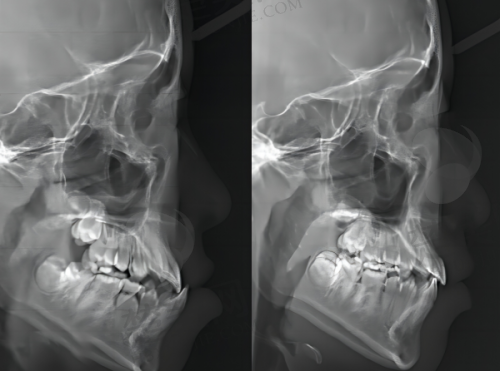

我们来看看其他一些口腔机构的情况,以便更好地了解杭州洁雅口腔门诊部的特点。郑州金水佳洁雅口腔门诊部人气0.2,活跃6.8,诊疗科目包括口腔科、医学影像科(X线诊断专精限口腔)。它是持证上岗的正规机构,有正规医生坐诊、收费正规、设备正规,虽是私立口腔,但收费不贵,且没有隐形消费,比较受当地牙友的认可,被当地牙友称之为郑州牙科排名前十的机构。与之相比,杭州洁雅口腔门诊部同样正规靠谱,并且在杭州当地的多项口腔服务排名中表现出色。